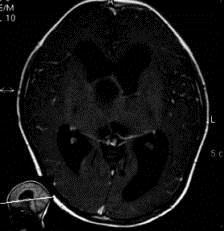

问题 病历摘要:??患者女性,6岁,半年来感觉视力模糊,近10天出现反复头痛,间有恶心呕吐,精神转差,查体:神志清楚,身高90cm,体重25Kg,血压90/55mmHg,右眼视力4.6,左眼视力4.8,双侧视乳头水肿,颈软,伸舌居中,四肢肌张力正常,肌力5级,双侧Babinski征(-)。 患者具有下列那些表现,可以诊断抗利尿激素分泌不当综合征?